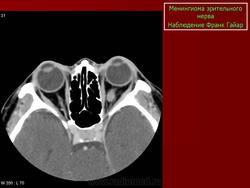

КТ-семиотика

На КТ срезах без контрастного усиления менингиома зрительного нерва выглядит изоденсной. Типично наличие линейных или точечных обызвествлений. Симптом «трамвайных рельс» отражает накопление КВ по сторонам гиподенсного зрительного нерва или наличие обызвествлений в структуре опухоли. Как правило, наиболее дистальная часть зрительного нерва, в месте его вхождения в глазное яблоко, не содержит обызвествлений.

При исследовании необходимо определить расположение бляшковидной менингиомы относительно бугорка турецкого седла и пластинки клиновидной кости, так как данный тип опухоли может распространяться интракраниально через канал зрительного нерва. КТ не позволяет адекватно визуализировать интракраниальное распространение опухоли, которое может привести к развитию двусторонней слепоты.